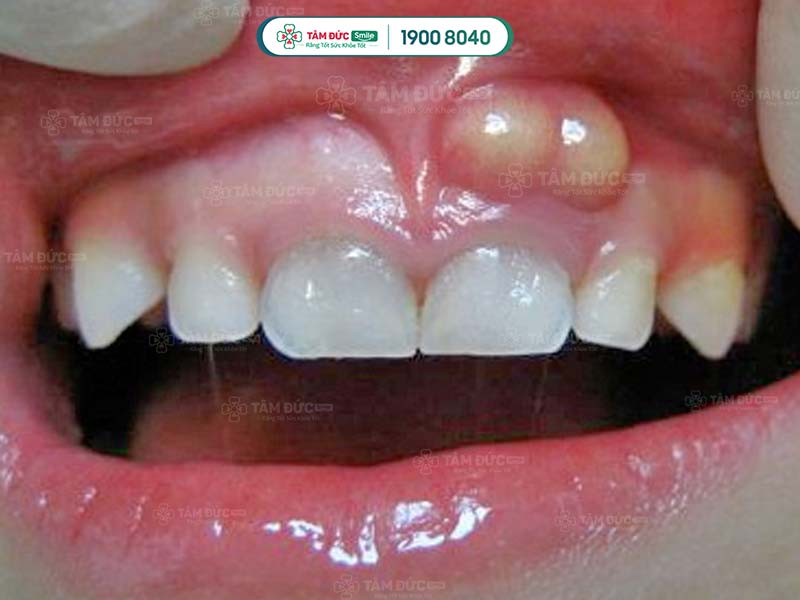

Giai đoạn này, vi khuẩn đã xâm nhập sâu hơn vào mô mềm và bắt đầu phát triển, tạo thành các ổ nhiễm trùng. Giai đoạn này có các triệu chứng lâm sàng rõ ràng hơn, bao gồm:

- Vùng sưng hiện rõ, sưng đỏ.

- Đau nhiều.

- Sốt, mệt mỏi, khó há miệng,....

Viêm mô tế bào răng làm vùng chân răng bị sưng tấy